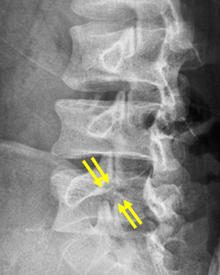

分離部修復術

腰椎分離症に対する手術は主に2つで、分離部修復術と椎体間固定術があります。椎間板の傷みがないもしくはあってもごく軽度か、20歳代までには適応となります。せなかを切開し、瘢痕組織や滑膜組織などの存在する分離部をきれいにして、自家骨(腸骨など)や人工骨などを移植します。移植した骨がしっかりつくように、スクリューやフックなどを用いて、分離部を圧着します。原則、手術翌日より硬性のコルセットを装着し、起立・歩行を開始します。十分に骨癒合が得られれば、後にインプラントを抜去しますが、必ずしも抜去しないこともあります。

第5腰椎分離症の術前レントゲン。矢印が分離部で骨が離れています。 -

第5腰椎分離症の術後レントゲン。分離部に骨が移植され骨癒合が得られています。